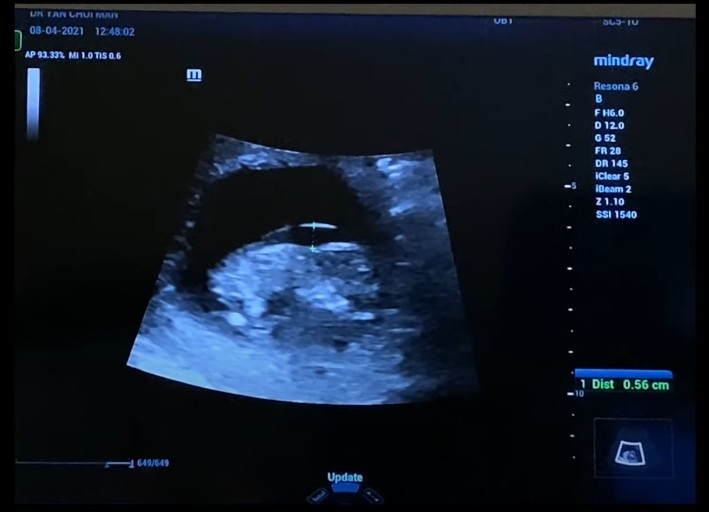

然而,今日Leanne就喺IG同YouTube 頻道宣佈自己懷上第三胎,並且已經做咗人工流產。佢喺接受產檢嘅時候,被告知胎兒可能患有唐氏綜合症,兩夫婦經過一輪商量之後,決定就算BB有呢個病都可以俾到足夠嘅愛同關懷佢。直到報告出咗,先知道胎兒係有一個極罕見嘅病「愛德華氏症T18」!

經過一輪檢查,醫生就話俾佢哋知呢個病係冇得醫治嘅,仲講出BB嘅問題:冇鼻骨、腸外露、腳係彎嘅等嚴重嘅缺陷,係一個畸胎。所以佢哋決定做人工流產,並且喺做手術之前先拍一家四口嘅孕照,因為佢話自己已經無法再承受一次失去孩子嘅痛楚,所以今次將會係佢最後一次懷孕!